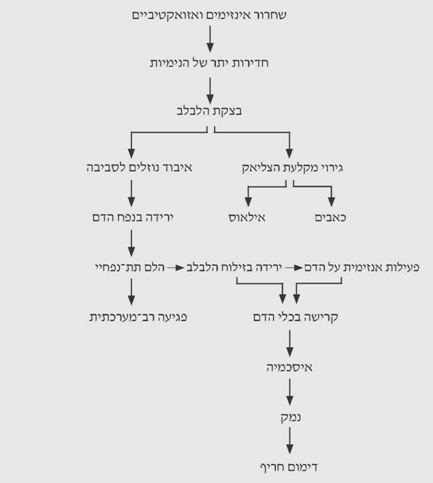

הנזק המקומי בלבלב גורם לשחרור פפטידים ואזואקטיביים, הגורמים לחדירות יתר של הנימיות בו. עקב כך, נוצרת בצקת בלבלב. בצקת זו, יחד עם הפעילות האנזימתית, גורמת לגירוי של מקלעת הצליאק, ועקב כך לכאבים ולחסימת מעי אדינמית. הבצקת גורמת לבריחת נוזלים סביב הלבלב, לעתים בכמות גדולה ביותר, המגיעה ל-6-5 ליטרים בתוך שעות, או ל-30%-20% מנפח הדם. הירידה בנפח הדם והעלייה בצמיגותו גורמים לעווית של המערכת הספלנכנית ולהלם תת-נפחי. עווית המערכת הספלנכנית מלווה בצבירת דם בכבד עד ל-40% יותר מהכמות המצויה בו, וגורמת לירידה בזרימת הדם השערית ולעלייה בזרימה הלימפתית. ההלם התת-נפחי גורם לפגיעה רב-מערכתית מצד אחד, ולפגיעה נוספת בלבלב מצד שני. הירידה בזילוח (פרפוזיה) הלבלב והפעילות האנזימתית במערכת הדם גורמות לקרישה בכלי הדם בלבלב, לאיסכמיה מקומית, לנזק ללבלב ולכלי הדם הגדולים. הדמם המסיבי הנגרם בעקבות זאת עלול להביא לידי מוות (תרשים 2.9).

הפגיעה הרב-מערכתית כוללת: פגיעה במערכת קרישת הדם - קרישה תוך-כלית מפושטת (DIC). ה-DIC היא לרוב מעבדתית. נדיר למצוא DIC קלינית. ה-DIC נובעת משפעול מערכת הקרישה על-ידי האנזימים הלבלביים, וכן משימוש בגורמי קרישה עקב קרישת הדם סביב הלבלב הניזוק.

המערכת הלבבית נפגעת עקב יצירת פפטיד קצר, שהוא בעל השפעה טוקסית על שריר הלב ונקרא לכן ה- MDF (Myocardial depressing factor). נזק זה גורם בחולים אלה הפרעות קצב וכישלון לב עד הלם לבבי (קרדיוגני), המצטרף להלם התת-נפחי.